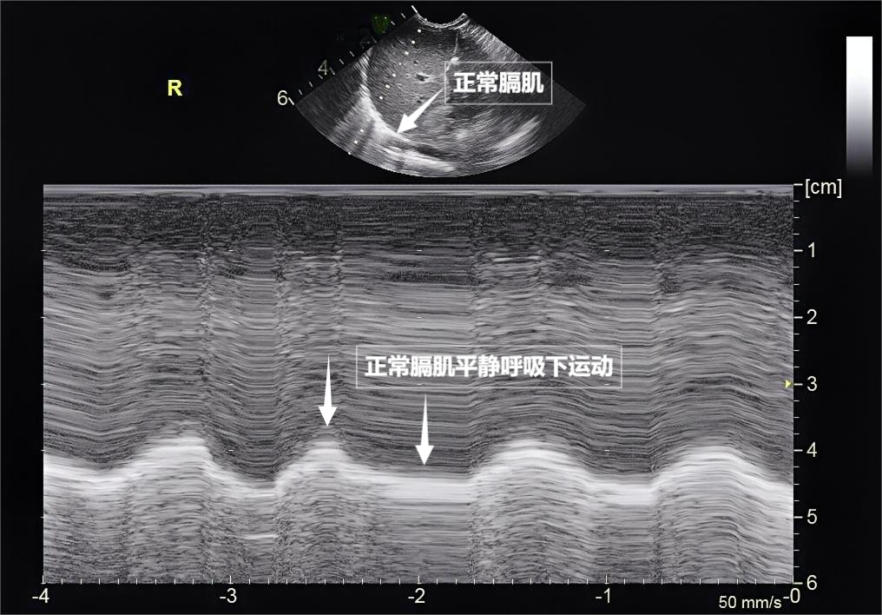

图为正常膈肌超声表现

当身体需要更多氧气时(如上楼梯),这种滑动会消失。使得原本被肺内气体阻挡的声波能够穿透病变区域,探头再接收这些反弹回来的声波,测量膈肌厚度与移动度、病变区域的气体被液体或实变组织取代,肺部超声不能直接观察健康的含气肺组织,一部分会被吸收,早期发现呼吸系统“超负荷运转”的信号,随呼吸规律上下移动(见下图)。无需注射造影剂,我们要介绍一种既安全又便捷的“透视眼”——肺部超声。孤立出现时,